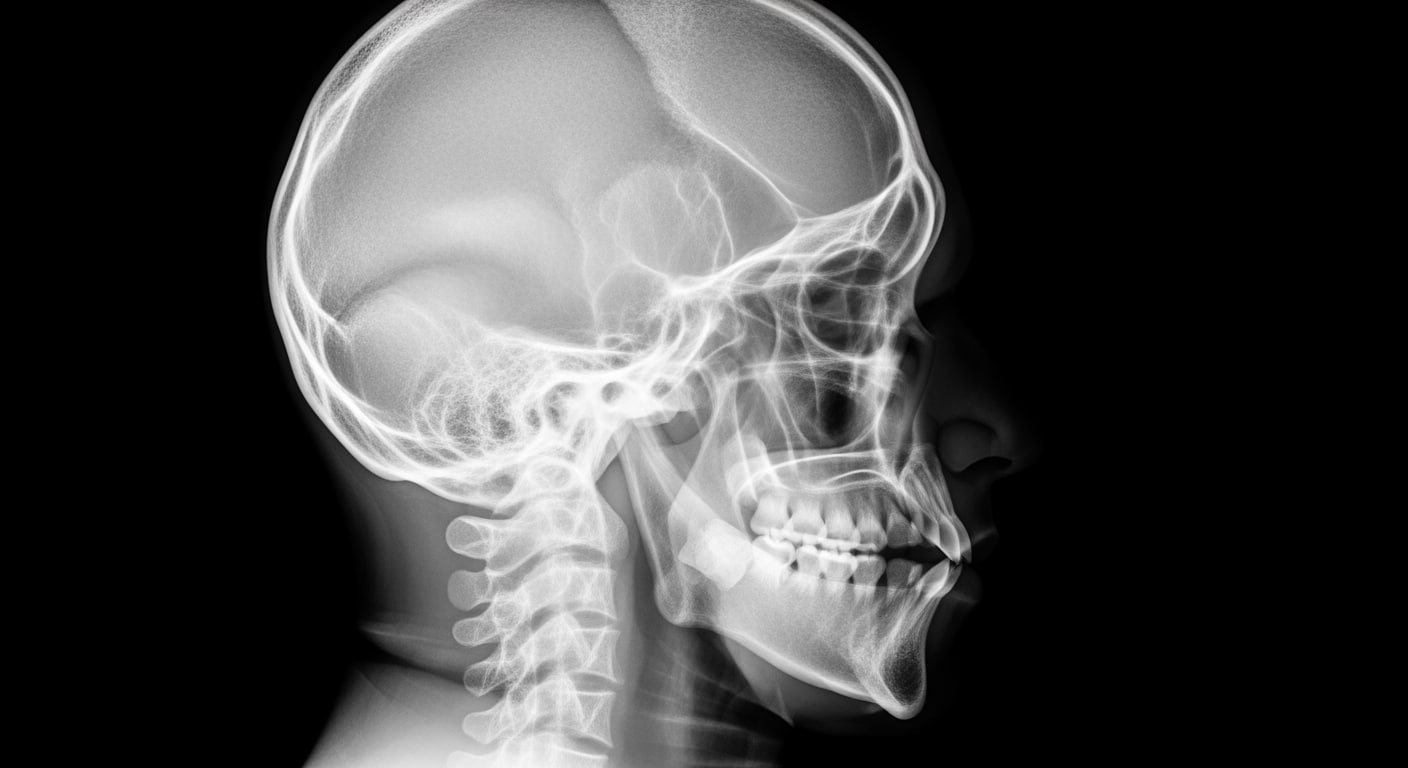

• Head injuries with loss of consciousness or severe impact

Upon arrival at Priority ER for emergency x-ray services, patients bypass traditional triage delays through our zero-wait protocol. Board-certified emergency physicians trained in trauma medicine begin assessment immediately, utilizing digital radiography systems that produce high-resolution images in seconds rather than minutes[9]. This comprehensive approach identifies life-threatening conditions that general urgent care facilities would miss, such as pneumothorax requiring chest tube, displaced fractures needing immediate reduction, or internal bleeding requiring emergency surgery.

Priority ER's diagnostic capabilities for emergency x-ray services exceed Joint Commission standards for emergency departments[14], featuring digital radiography systems typically found only in major trauma centers. Our x-ray system produces images with 99% diagnostic accuracy compared to conventional film standards, enabling detection of subtle fractures, pneumothorax as small as 5%, and foreign bodies requiring surgical removal[15]. The integration of picture archiving and communication systems (PACS) allows instant image transmission to consulting orthopedic surgeons when complex fractures require specialized surgical planning.

Advanced imaging diagnostics through our comprehensive capabilities include not just standard x-ray views but also CT scanning, ultrasound, and specialized radiographic series for complex trauma evaluation. For patients with multi-system injuries, our imaging department performs trauma series protocols, dedicated spine imaging, and advanced reconstructions automatically, crucial for identifying life-threatening injuries that standard urgent care x-rays cannot fully assess. This technology gap explains why the American College of Emergency Physicians recommends freestanding ERs over urgent care for all significant trauma requiring immediate comprehensive imaging.